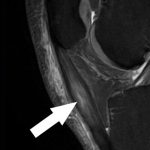

- NMR beeld van ernstige ontsteking en scheur in onderste deel achillespees

- NMR beeld van ernstige inflammatie bovendeel patellapees (Apexitis Patellae of Jumper’s Knee)